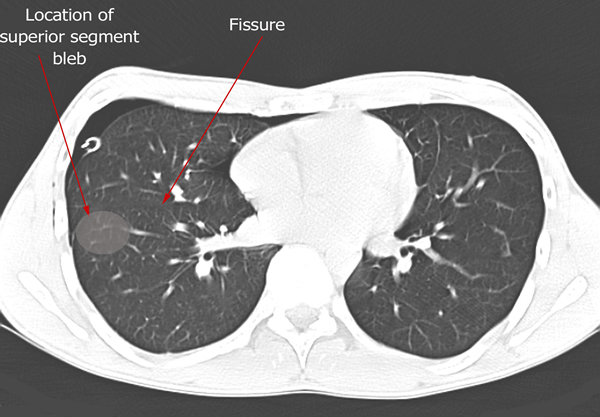

Figure Ct Bulla Ct Scan Pneumothorax Contributed By Steve Bhimji Ms Md Phd Statpearls Ncbi Bookshelf

Figure Ct Bulla Ct Scan Pneumothorax Contributed By Steve Bhimji Ms Md Phd Statpearls Ncbi Bookshelf from www.ncbi.nlm.nih.gov